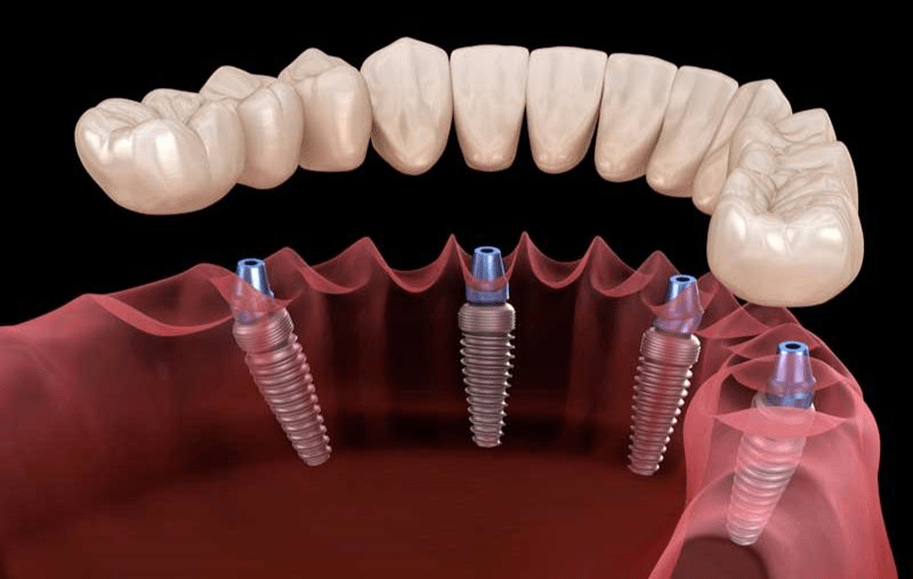

کاشت دندان یا ایمپلنت به این معنا است که فرد با انجام آن قصد دارد جای خالی یک یا چندین دندان را پر کند. ایمپلنت کامل دهان را میتوان شیوهای ساده برای جایگزین کردن دندانهای آسیب دیده یا از دست رفته دانست. آنها عملکردی شبیه به ریشه دندان خواهند داشت و از پایهای مستحکم جهت اتصال به فک برخوردار هستند. در شرایطی که عدم وجود دندانها در یک فک یا هر دو فک گسترش داشته باشد، فرد از شرایط استفاده از ایمپلنت کامل دندانی برخوردار خواهد بود. مزیتهای این روش در مقایسه با سایر درمانهای سنتی همچون دندان مصنوعی بسیار هستند. انواع مختلفی از ایمپلنت کامل دهانی نیز وجود دارند.

پیش از انجام ایمپلنت کامل دهان، شرایط و وضعیت دهان شما مورد بررسی قرار میگیرد. در روش فول موس بسته به شرایط خاص دهانی شما، امکان دارد که به چهار تا هشت ایمپلنت در فک بالا و چهار تا هشت ایمپلنت در فک پایین نیاز داشته باشید. این روش درمانی برای افرادی به کار گرفته میشود که جای خالی بسیاری از دندانها را در دهان خود حس میکنند. در این شیوه از درمان، ایمپلنت دندانی در استخوان فک قرار داده میشود و دیگر پروتزهای دندان تحت حمایت این ایمپلنتها قرار میگیرند.

- متخصص پیش از نصب پایههای ایمپلنت، اقدام به آماده سازی استخوانهای شما جهت قرار دادن پایهها میکند. در شرایطی که استخوان فرد تحلیل رفته باشد، پیش از نصب پایه، پیوند استخوان انجام میگیرد.

- پس از اینکه استخوانهای فرد آماده شد، جراحی ایمپلنت کامل صورت میگیرد. متخصص ایمپلنت، پایههای ایمپلنت را داخل استخوان تعبیه میکند.